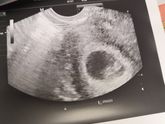

22 октября 2019 21:45 Была сегодня планово у врача, сдала бак посев на эту жуткую уреаплазму... Малыша уже смотрели не вагинальным датчиком, обычным? все хорошо, сердечко бьется 176 ударов в минуту, это норма на моем сроке) Все остальные показатели крови, мазков близки к … Читать далее